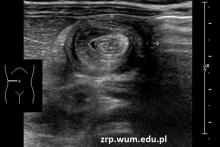

Przypadek 35: 2-miesięczna dziewczynka z epizodami bólu brzucha o charakterze kolki.

Rozpoznanie: W badaniu USG w okolicy podwątrobowej uwidoczniono czoło wgłobienia krętniczo-kątniczego. Przy czole wgłobienia kilka drobnych węzłów chłonnych. Wykonano udaną próbę odgłobienia wlewem wodnym.